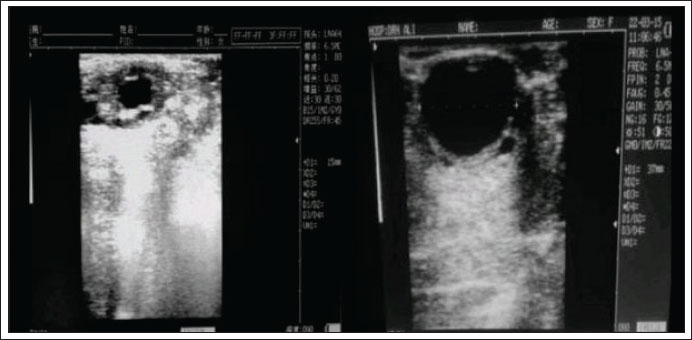

For estrus detection, cows with onset characteristics were classified every 6 hours. Both NO and DO cows had the same estrous cycle duration of 20–25 days. Variations in estrus duration, ovulation time, and insemination per gestation were observed. The data showed that DO cows had significantly higher values (p < 0.05) than controls NO for all parameters (Table 1). During pre-onset estrus, DO cows had significantly smaller follicle diameters (1.34–1.44 cm) than Normal cows (NO) cows (p < 0.05), but instead experienced enlargement after the onset of estrus, which should have undergone lysis due to the ovulatory process (Fig. 1).

Fig. 1. Diameter size of the de Graaf follicle in DO and NO cows This figure illustrates a comparison of follicle diameters between normal cows (left) and those with D-0 estrus (right) at the onset of estrus. The Graafian follicle diameter in normal cows is 1.5 cm, which is significantly smaller than that in cows experiencing delayed ovulation, where it exceeds 3 cm.